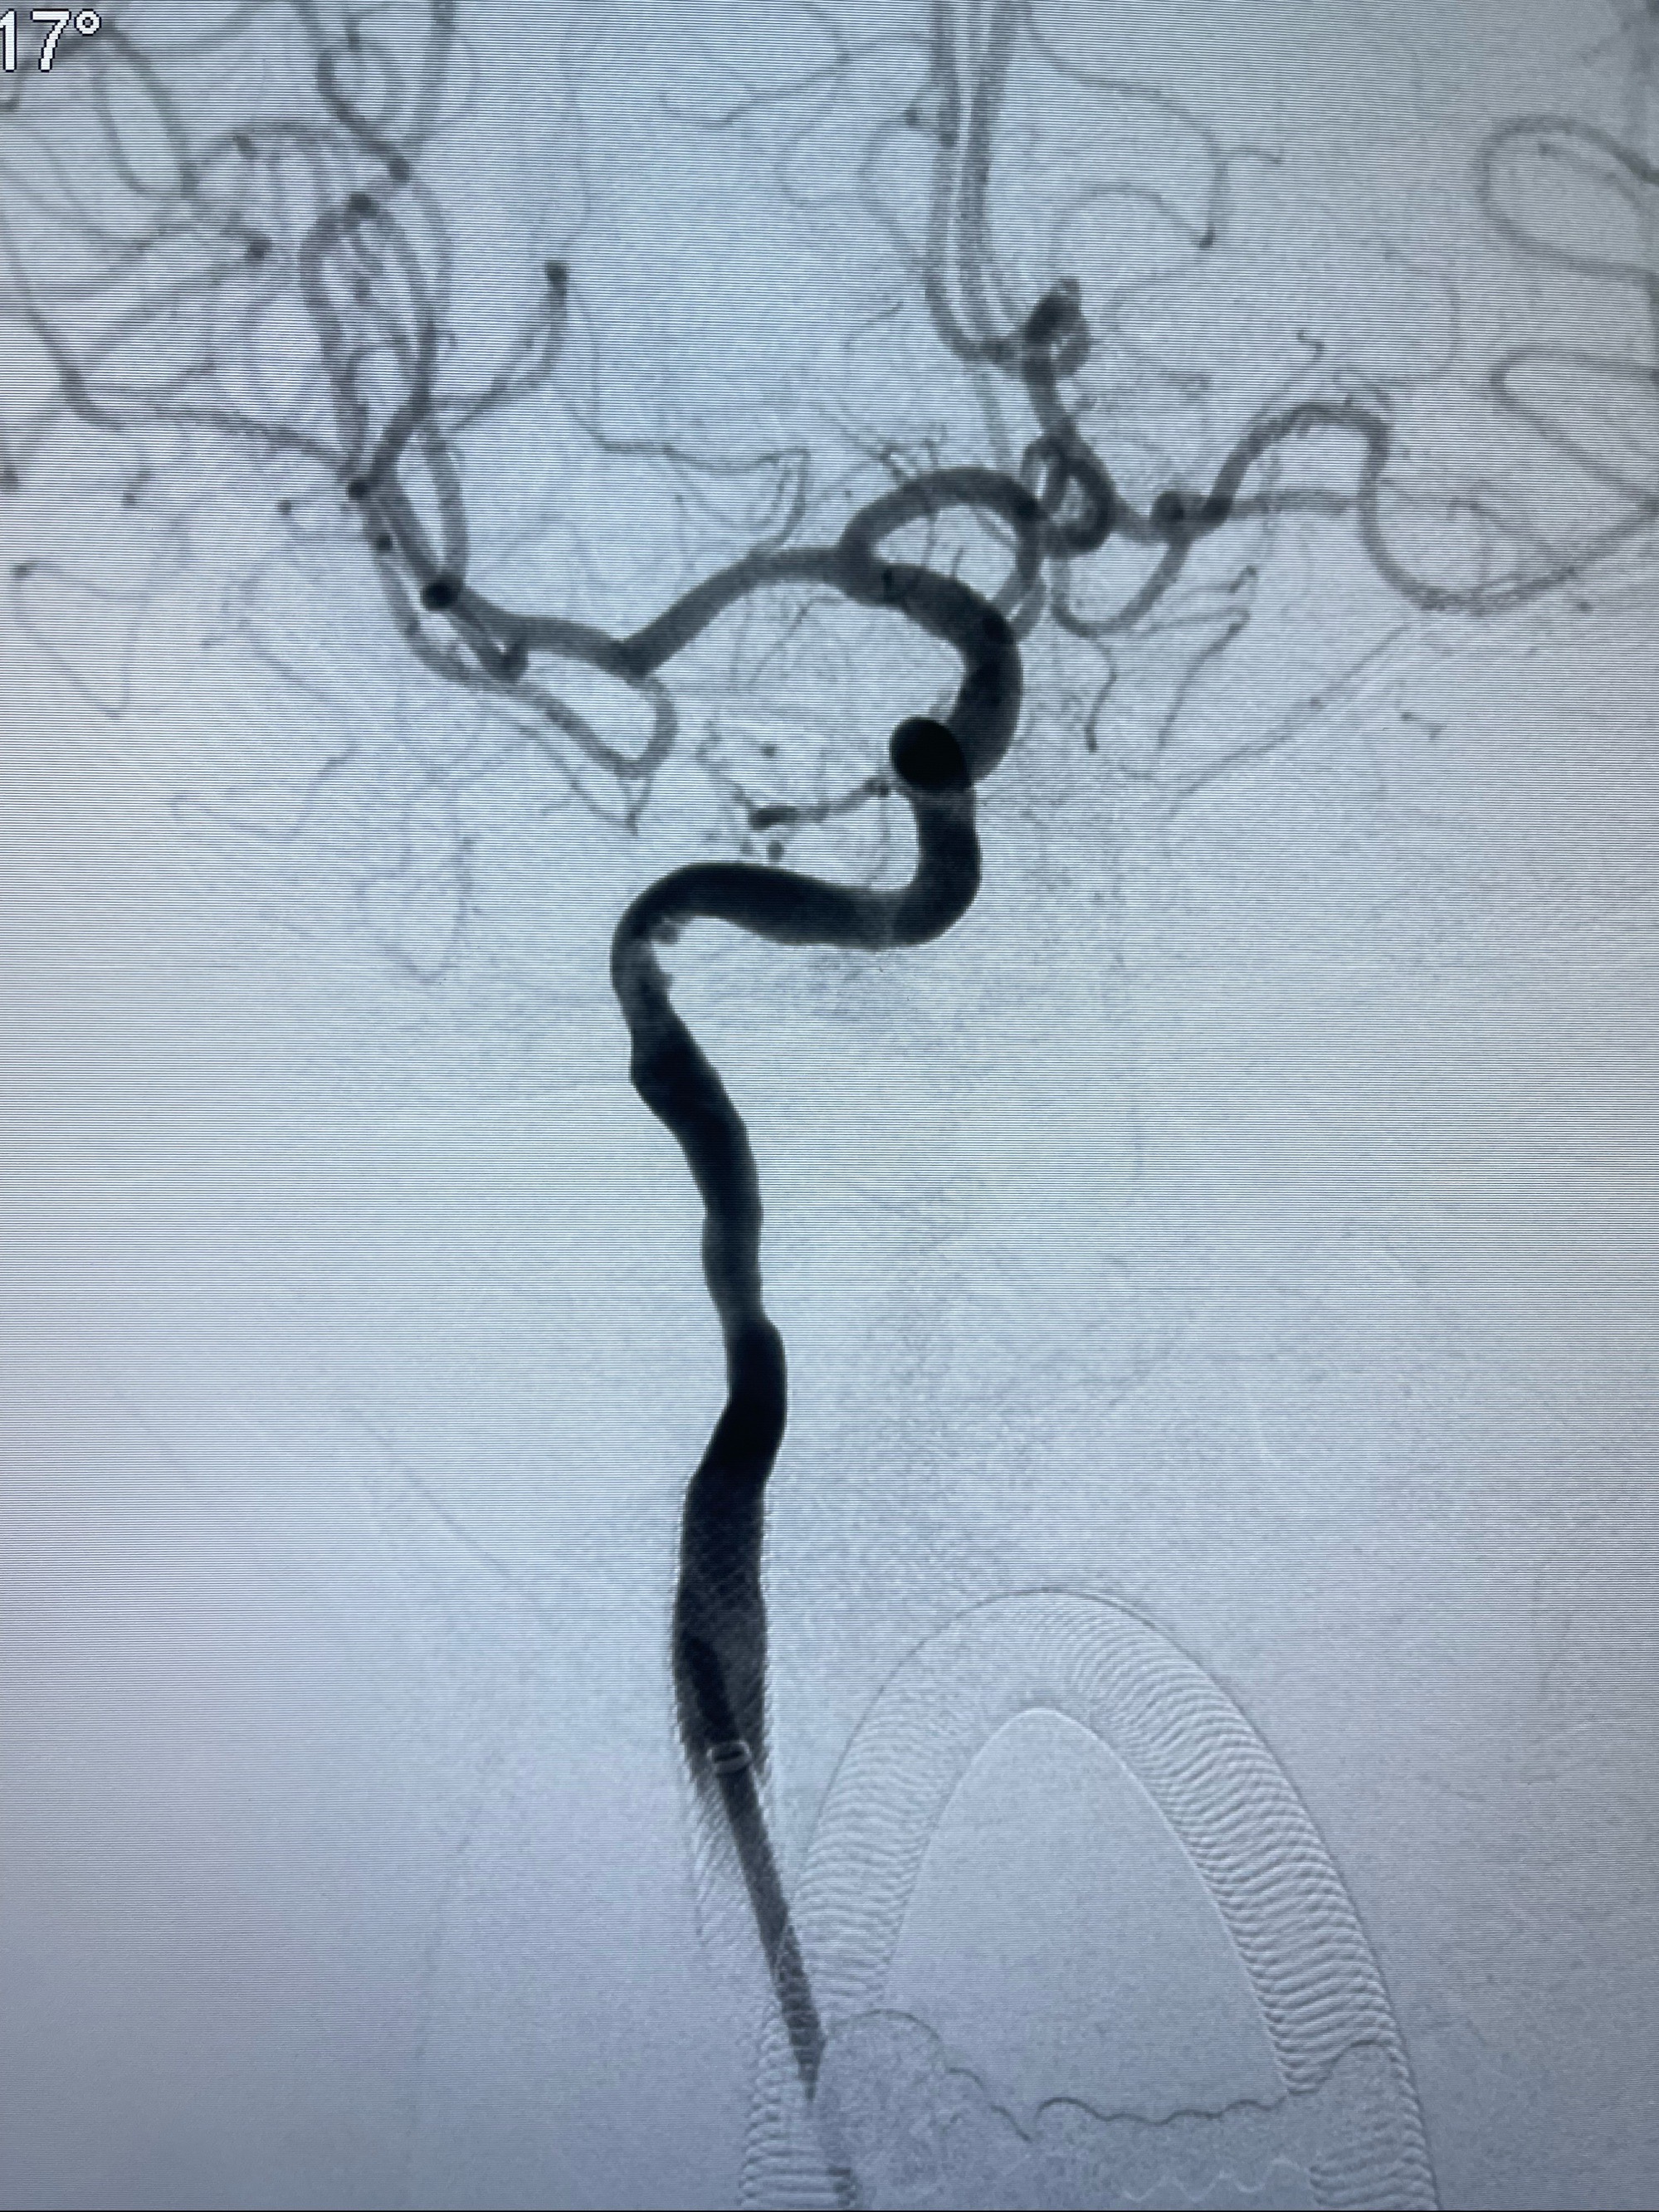

2023-07-10DSA:右侧颈内动脉岩骨段夹层伴中偏重度狭窄改变,左侧颈总动脉闭塞、右侧颈外动脉由右侧肋颈干甲颈干吻合代偿

箭头所示为颈内动脉岩骨段重度狭窄,结合MRI,考虑为肿瘤侵犯右侧颈内动脉

箭头以近至支架段管腔不规则狭窄

MRI:显示肿瘤侵犯右侧颈内动脉岩骨段上下,向下至原颈内动脉支架远心段,向上至颅底

经导引导管造影显示支架远端颈内动脉不规则狭窄伴局部充盈缺损,同时行全身肝素化5ml